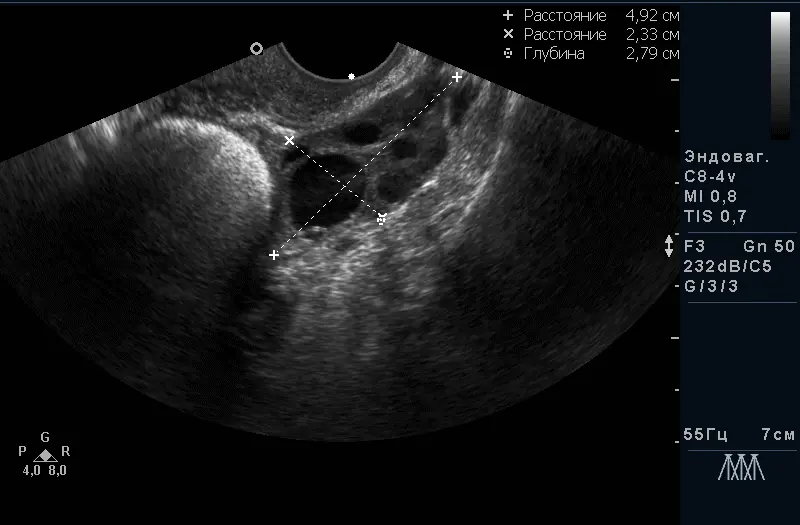

Трансвагінальний доступ є “золотим стандартом” в дослідженні органів малого таза на увазі найкращою візуалізації з найтоншої оцінкою структури, оптимальний метод в діагностиці вагітності на ранніх термінах, оцінці будови плода до 14 тижнів. Датчик розташовується в піхві.

За допомогою УЗД можна побачити і оцінити стан тіла матки, шийки матки, яєчників, маткових труб (при їх патології) і оточуючих їх органів. Є пріоритетним методом дослідження стану судин малого таза. Під час дослідження вимірюються розміри всіх доступних для дослідження органів, оцінюється їх структура і відповідність фазі менструального циклу, оцінка кровопостачання органів і судин.